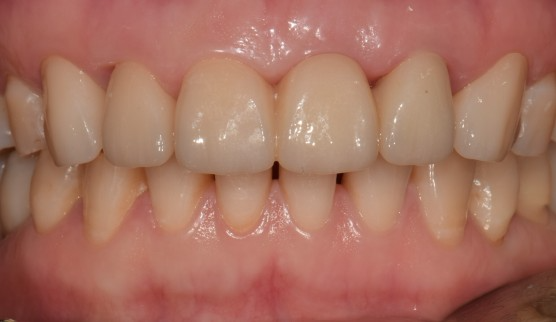

치료명 : 신경치료 및 지르코니아관 수복, 임플란트

#21.22 정출, #21발치 설명드림. #131211X2223 브릿지 진행